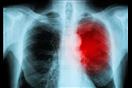

وعلى الرغم من أن عدوى القلب الحادة نادرة في معظم الحالات، إلا أن انتشار عدوى القلب ازداد بين فئات سكانية معينة، وكشفت دراسة نشرت عام 2020 في مجلة Circulation أن الإصابة بالتهاب الشغاف، وهي عدوى قلبية تحدث عندما يتعرض القلب للبكتيريا أو الفيروسات أو الفطريات، ويتسبب الالتهاب الناجم عن عدوى القلب في تلف أي جزء من القلب، وفقا لموقع " healthdigest".

والتهاب التامور هو التهاب يصيب السطح الخارجي للقلب، والتهاب الشغاف هو التهاب يصيب بطانة صمام القلب، والتهاب عضلة القلب هو التهاب يصيب عضلات القلب.